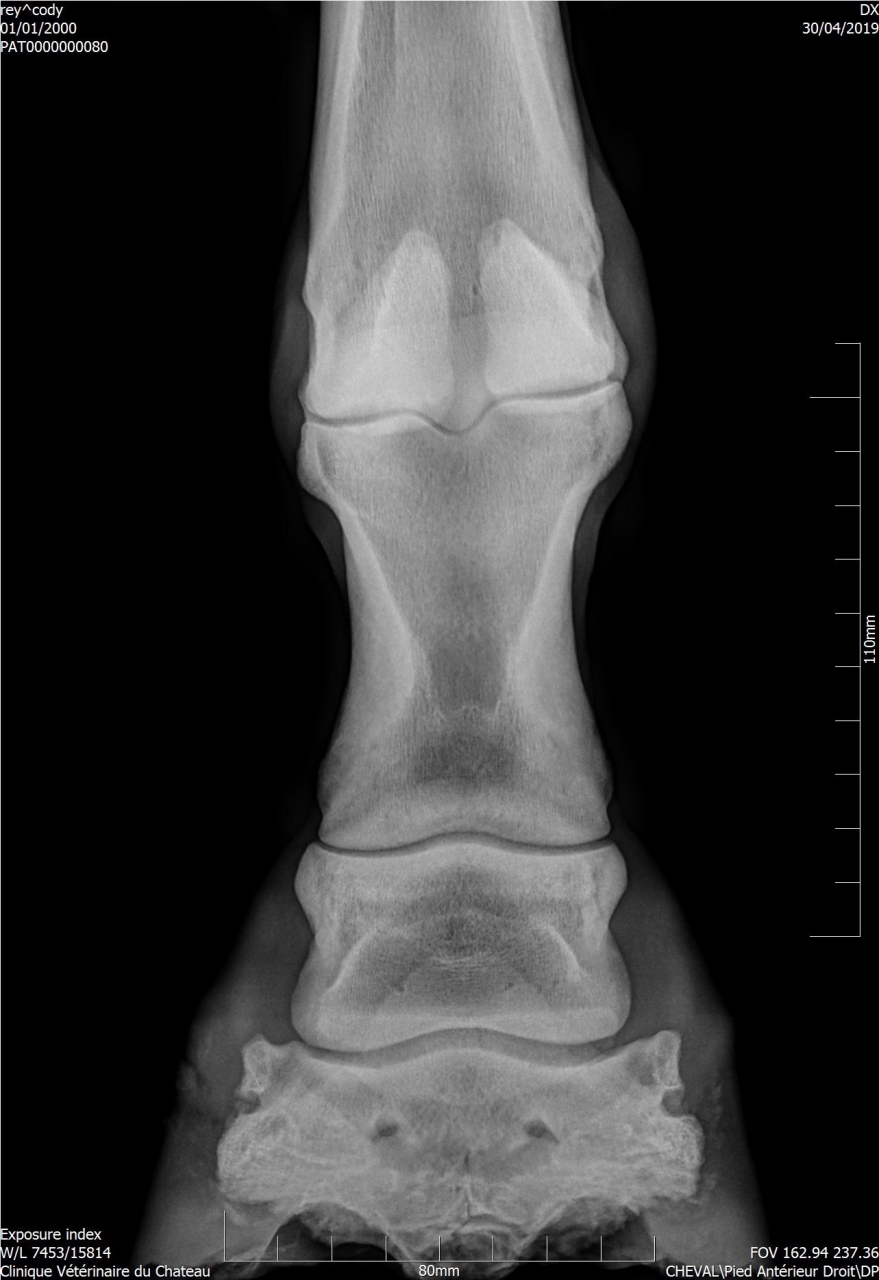

| Dire merci | Dimanche j'ai longé Cody et il est irrégulier au trot. Il a tendance à se coucher sur le cercle à main droite. J'ai du mal à voir d'où provient la boiterie. J'ai plus l'impression qu'il est raide. Je prends toujours le temps de l'échauffer au pas aux 2 mains et de faire un assez grand cercle. Je ne longe pas très longtemps. Avant que je l'achète il a eu une grosse plaie non soignée à l'antérieur droit. ![]() Lors de la visite d'achat du 12/12/2017, la véto a indiqué : Déformation des tissus mous en regard de l'épaississement cutané consécutif au chéloïde cicatrisé face dorsale du boulet, sans atteinte osseuse associée. J'ai fait réaliser des radios. ![]() ![]() La boiterie pourrait elle être une conséquence du chéloïde ? Les tendons sont normaux. Je vais sans doute faire passer l'osteo dans un premier temps. D'autres tests à faire pour déterminer l'origine de cette boiterie ? |

| Dire merci | Voici le compte-rendu du véto : Examen général: L’examen locomoteur au pas et au trot en ligne droite ne met pas en évidence de boiterie. Le cheval pose l’antérieur droit en deux temps : pose d’abord en muraille externe puis en interne. Une boiterie 2/5 de l’antérieur gauche apparait sur le cercle au trot à droite Examens complémentaires : Radiographie : Pieds de face : 3-4 fossettes synoviales sur le bord distal du naviculaire antérieur droit, de profondeur faibles et peu ouvertes. 2-3 fossettes synoviales dont l’une plus ouverte sur le bord distal du naviculaire antérieur gauche Léger pincement articulaire p1-p2 et p2-p3 coté externe visible sur le membre à l’appui. Boulet de face : Petit remaniement osseux au niveau de l’insertion proximale du ligt coll int Boulet et pieds ant droit de profil : ras La boiterie étant trop légère pour préciser la localisation par anesthésie étagée, plusieurs hypothèses sont envisagées. Par ordre d’importance : • Pincement et fatigue articulaire lié au parage ou à une compensation d’une légère entorse boulet • Entorse du boulet • Début syndrome podotrochléaire Message édité le 14/05/19 à 18:37 |